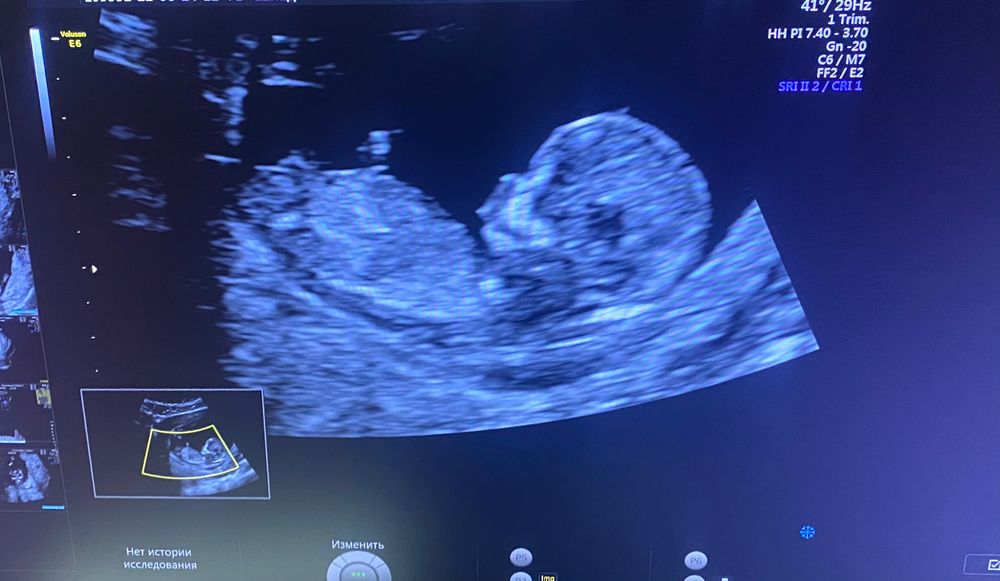

Какой пол? 😂

Пол малышаДевочки, прошла первый скрининг сегодня, было очень волнительно))

Как думаете кто там сидит? мальчик или девочка?) на узи не сказали и даже не предположили. может по фото будет не понятно) ну а вдруг 😂😂😂